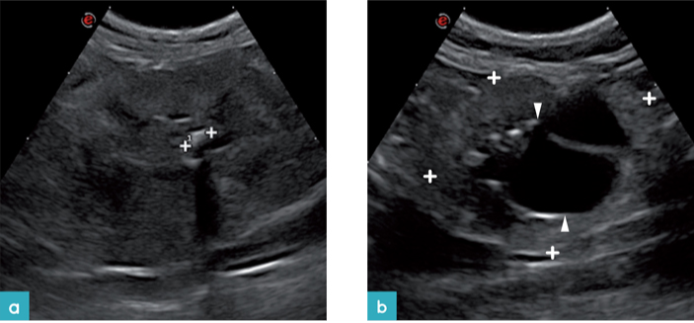

老年猫通常会患有慢性肾脏病(CKD)。患有慢性肾脏病的超声波变化是肾脏较小(<3.2厘米),并且肾脏轮廓不规则、皮质与髓质交界处不清晰,肾实质异质性、肾髓质局灶性或弥漫性过度再生、髓质环征、肾实质梗塞及或钙化(图9 -11.视频4和5)。但如果只有以上的其中一个病征是不足以诊断猫患有慢性肾脏疾病的。在疾病的最后阶段,肾脏会非常小、极不规则,并且其回声结构完全改变,其中可能包括高回声病灶,具有或不具有钙和磷酸盐沉积相对应的声影(图12)。偶尔,由于肾脏的异常结构,这些病患的肾脏只能从其位置识别出来,而不是通过它们显示的正常超声回波结构。有时会观察到所谓的“大肾,小肾”综合征,其病理表现为其中一个肾脏体积明显减小,另一个肾脏体积有所增加。进行肾活检的组织病理学研究是确定导致慢性肾脏疾病病变类型所必需的。重要的是要考虑到超声诊断与肾功能无关,并且这也不是预测猫发展为氮血症的好办法。